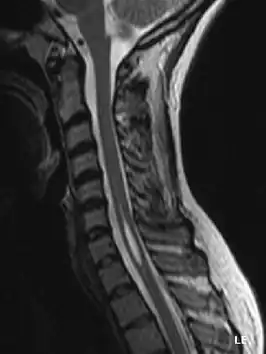

Syringomyelie is een zeldzame neurologische aandoening waarbij het ruggenmerg wordt aangetast, meestal vooral ter hoogte van de nekwervels, en het centrale kanaal in het ruggenmerg waardoor het wijder wordt.

De naam komt van het Grieks syrinx, een rieten buisje of fluitje en is gebaseerd op dit wijdere dan normaal kanaal dat bij pathologisch anatomisch onderzoek kan worden waargenomen. Tegenwoordig is de diagnose ook al bij levende patiënten te stellen door middel van MRI-onderzoek.

Syringo(hydro)myelie is ook een gevolg van chiarimalformatie, een aandoening waarbij het achterhoofdsgat (foramen magnum) afwijkt van de normale grootte. De punten van de kleine hersenen puilen daardoor uit (bij een te klein achterhoofdsgat) of zakken (bij een te groot achterhoofdsgat). Het gevolg is dat de doorstroming in het ruggenmergsvocht niet verloopt zoals het hoort (syringomyelie). Hierdoor kan dan een waterhoofdje (hydrocefalus) ontstaan. Chiarimalformatie komt maar heel weinig voor.